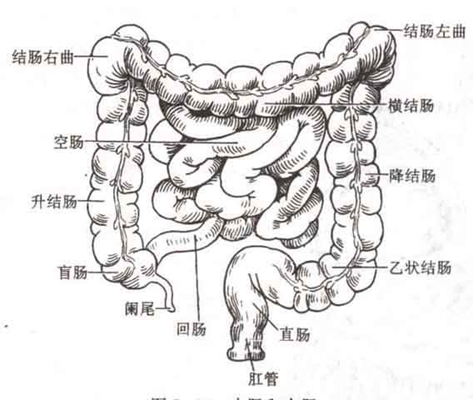

盲腸炎圖片

盲腸的位置 (50)

盲腸的位置 (6)

盲腸的位置 (7)

盲腸的位置 (8)

盲腸的位置 (9)

盲腸的位置 (46)

盲腸的位置 (47)

盲腸的位置 (48)

盲腸的位置 (49)

盲腸的位置 (5)